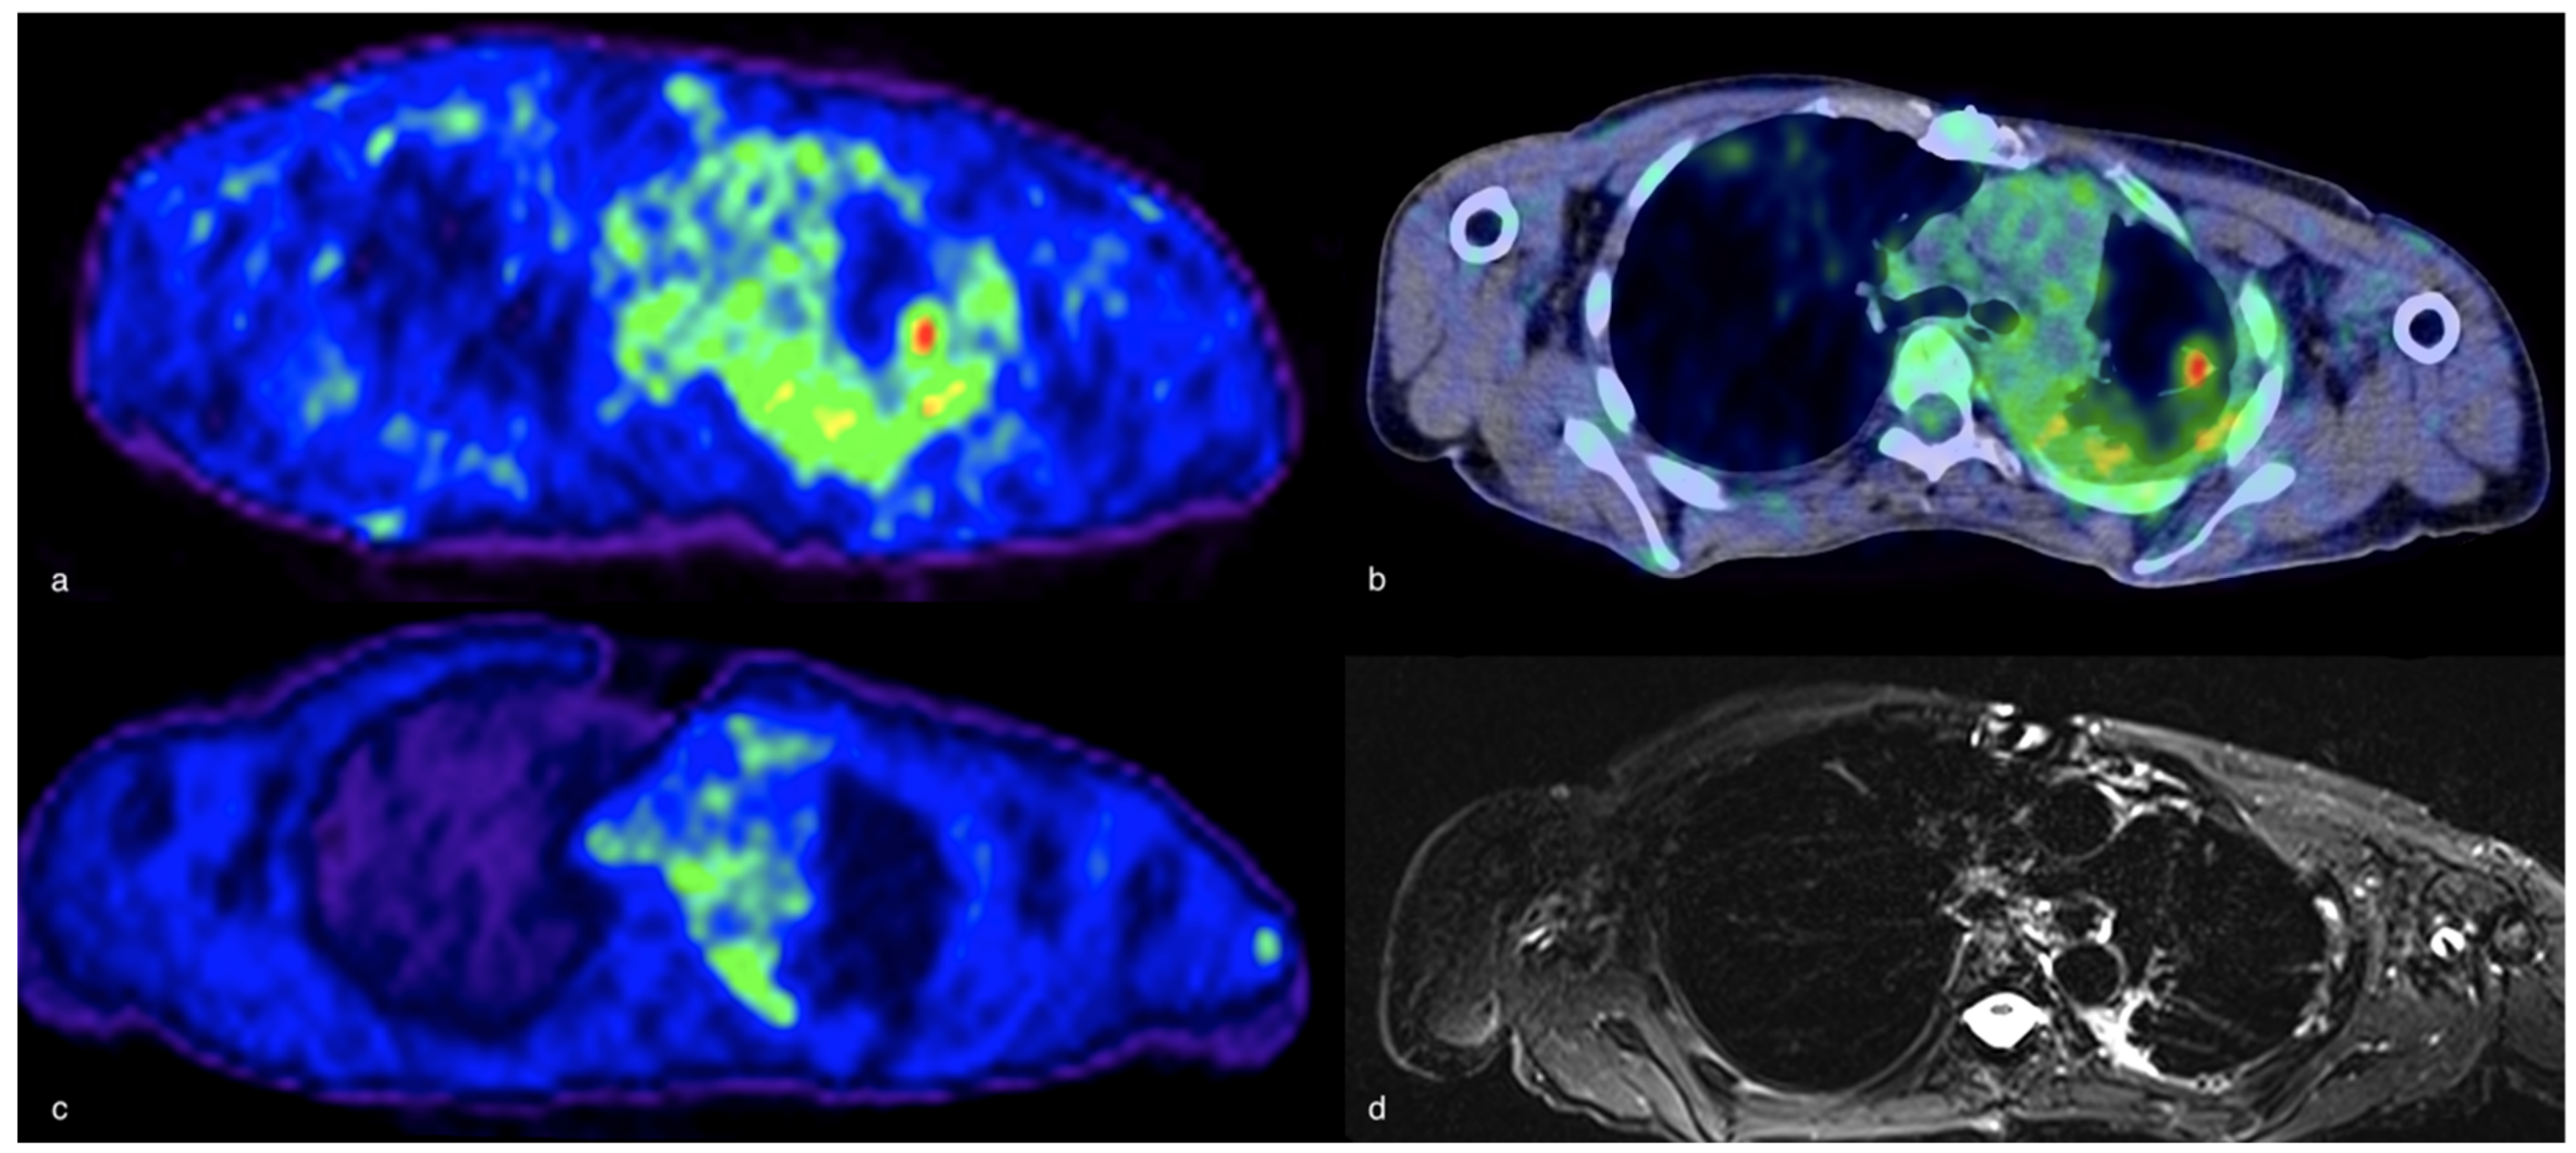

- Thomas, B.A.; Molton, J.S.; Leek, F.; Pang, Y.; Totman, J.J.; Paton, N.I.; Townsend, D.W. A comparison of 18F-FDG PET/MR with PET/CT in pulmonary tuberculosis. Nucl. Med. Commun. 2017, 38, 971–978. [Google Scholar] [CrossRef] [PubMed]

- Heusch, P.; Köhler, J.; Wittsack, H.J.; Heusner, T.A.; Buchbender, C.; Poeppel, T.D.; Nensa, F.; Wetter, A.; Gauler, T.; Hartung, V.; et al. Hybrid [18F]-FDG PET/MRI including non-Gaussian diffusion-weighted imaging (DWI): Preliminary results in non-small cell lung cancer (NSCLC). Eur. J. Radiol. 2013, 82, 2055–2060. [Google Scholar] [CrossRef]

- Heusch, P.; Buchbender, C.; Köhler, J.; Nensa, F.; Gauler, T.; Gomez, B.; Reis, H.; Stamatis, G.; Kühl, H.; Hartung, V.; et al. Thoracic staging in lung cancer: prospective comparison of 18F-FDG PET/MR imaging and 18F-FDG PET/CT. J. Nucl. Med. 2014, 55, 373–378. [Google Scholar] [CrossRef]